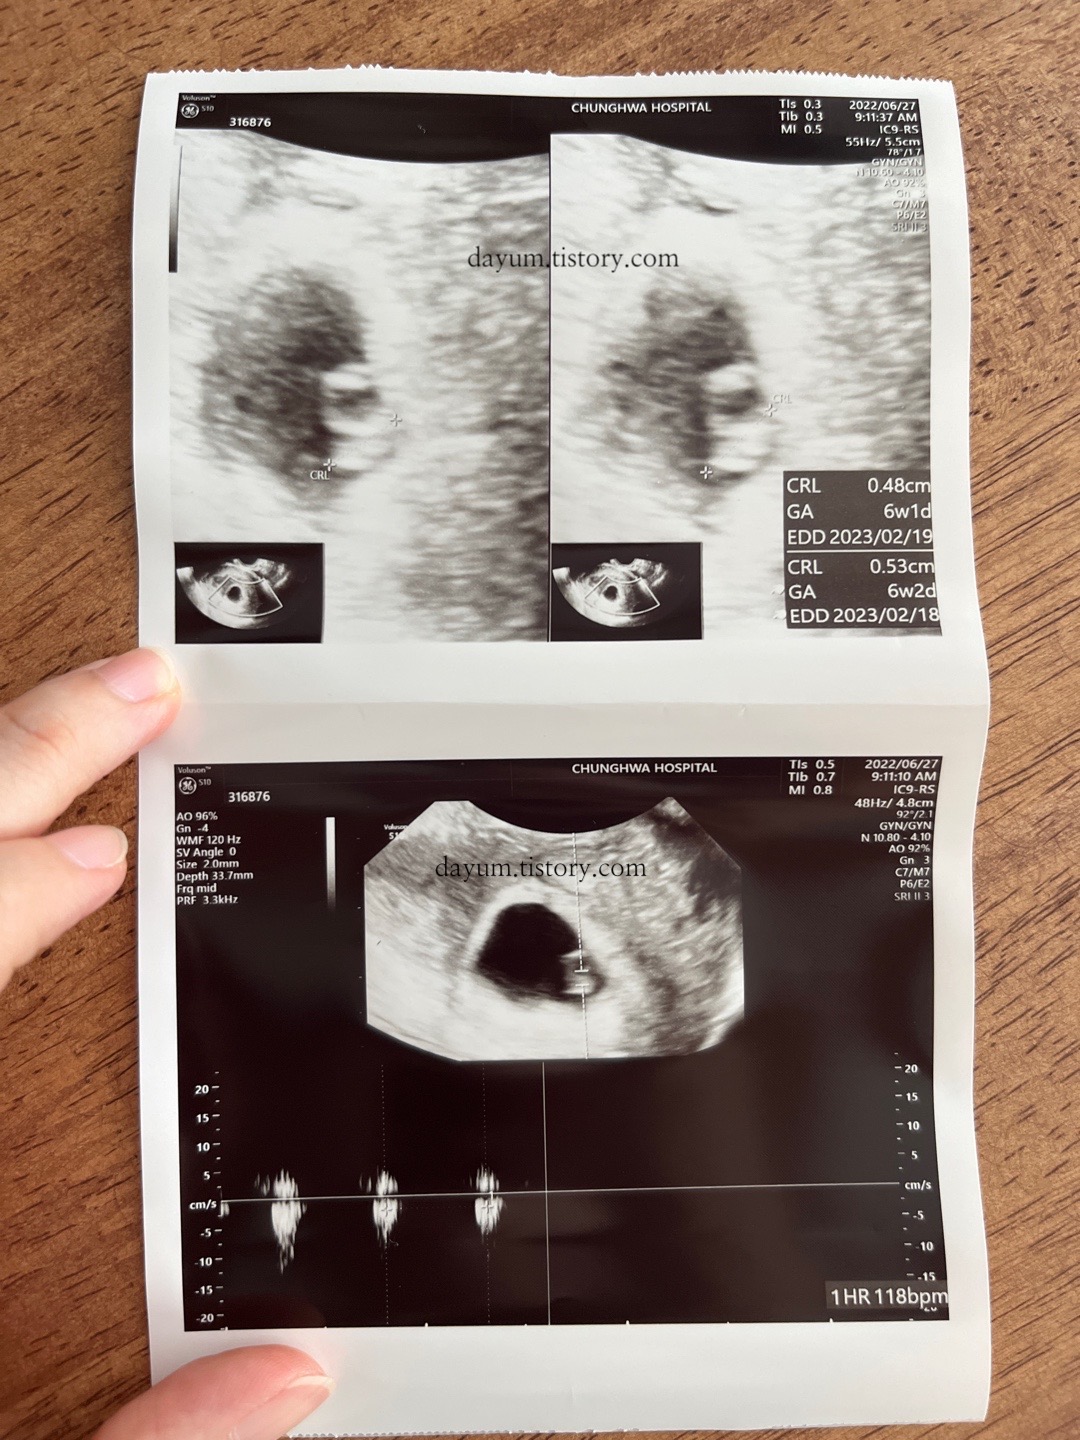

6주 2일과 8주 2일의 초음파 사진 차이

0.53cm의 크기에 심박수는 118bpm / 2.06cm의 크기에 심박수는 171bpm

2주 동안 1.6cm정도 자랐다.

8주 2일이지만 8주 5일 정도의 크기라고 한다.

탯줄과 팔, 다리가 생겼다.